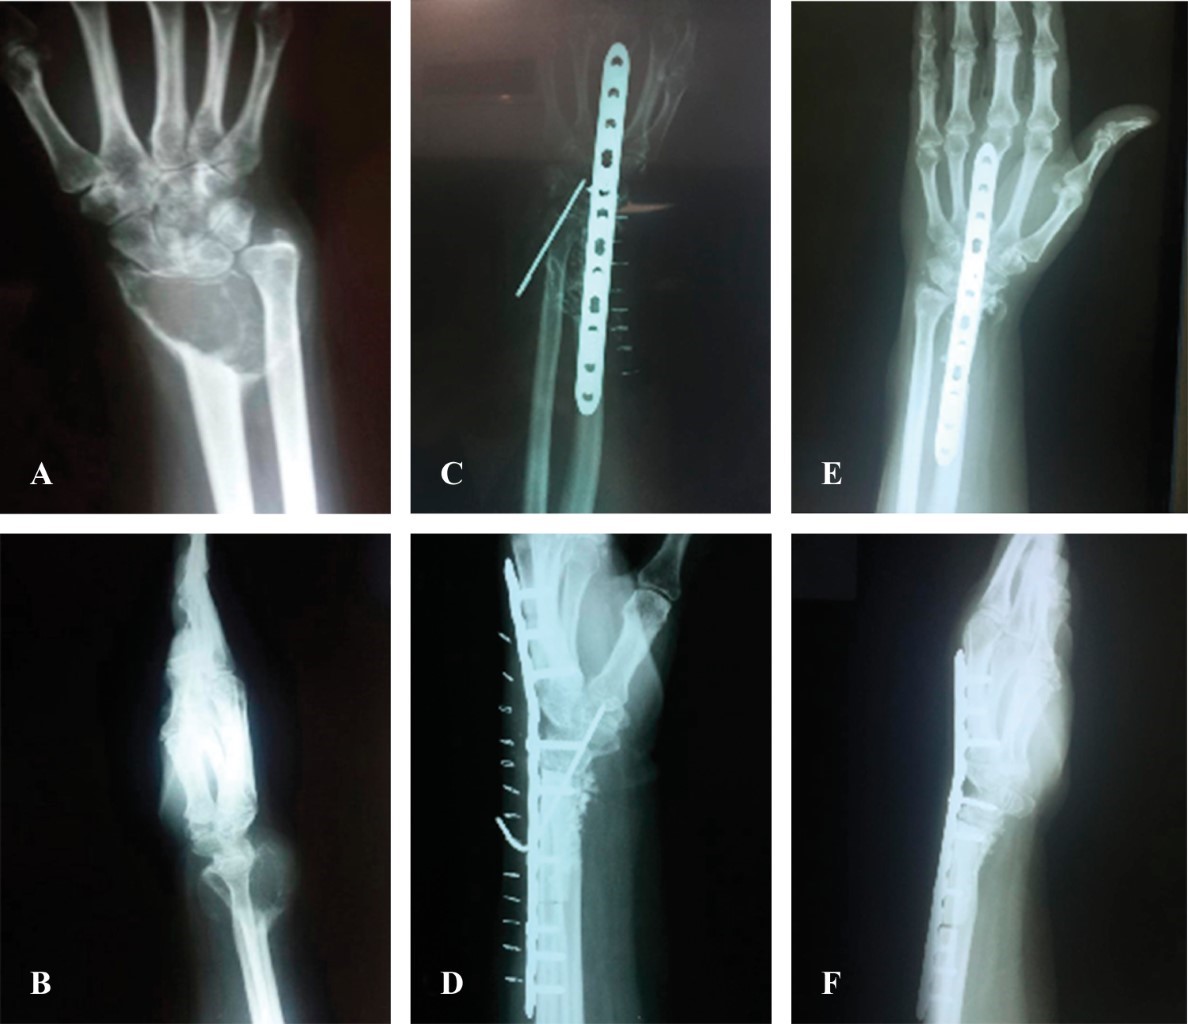

Low-cost reconstructive treatment after resection of distal radius giant cell tumor

Introduction: giant cell tumor (GCT) is a benign intramedullary bone tumor that frequently arises at the ends of long bones. After the distal femur and proximal tibia, the distal radius is the third most affected site with particularly aggressive tumors. Our objective is the presentation of the clinical case of a patient diagnosed with distal radius GCT classified in grade III of Campanacci who received a treatment adjusted to her economic possibilities. Case report: a 47-year-old female, without economic solvency and with some medical service. Treatment included block resection, reconstruction with distal fibula autograft, and radiocarpal fusion with blocked compression plate. Eighteen months later, the patient had good grip strength (80% on the healthy side) and had fine motor function in the hand. The wrist presented stability with pronation of 85o, supination of 80o, flexion-extension of 0o and a score of 6.7 in the DASH functional outcomes assessment questionnaire. His radiological evaluation five years after his surgery continued with no evidence of local recurrence and pulmonary involvement. Conclusion: the result in this patient, together with the published data, indicate that the block tumor resection technique, plus distal fibula autograft and arthrodesis with blocked compression plate provide an optimal result of functionality for the grade III distal radial tumor at low cost.

Figure 1